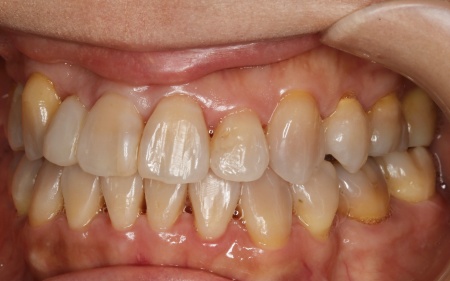

治療前

はじめの相談内容 「見た目が気になる。また、食べ物が噛みにくい」とご相談いただきました。

診断結果 拝見したところ、上下の歯がデコボコに乱れて生えていました。

歯の大きさに対して顎が小さいため、歯が正常に並びきらず、全体的な噛み合わせのバランスも崩れています。

噛み合わせを詳しく検査したところ、実際にしっかりと噛み合っているのは一部の歯だけで、このまま放置すると特定の歯に負担が集中し、将来的に痛みや違和感が生じるおそれがあります。

また、銀歯が装着されている右下奥歯は以前神経を抜く治療がされていましたが、現在は歯の具合が良好とはいえず、温存が難しい状態です。

以上のことから、温存が難しい歯を抜いたうえで、矯正治療によって歯並びと噛み合わせを整える必要があると診断しました。